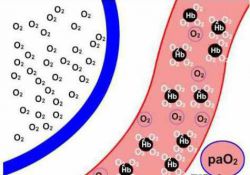

Защелачивание организма, или алкалоз, имеет множество причин, и его механизмы развития могут быть как внутриклеточными, так и системными. Известно несколько видов алкалозов: газовый, метаболический, выделительный, экзогенный и смешанный.